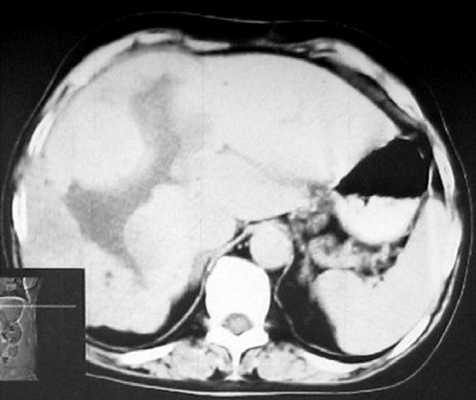

КТ брюшной полости. Печень увеличена в размерах, неоднородная по эхоструктуре, признаков портальной и билиарной гипертензии нет. В правой доле печени, занимая практически всю долю, определяется дополнительное объемное образование, неоднородно пониженной плотности, с неровными четкими контурами, размером 143х93 мм. После введения контрастного вещества образование неравномерно накапливает его от периферии к центру, в виде языков пламени. В центре образования определяется участок равномерно низкой плотности, продолговато-ветвистой формы, с четкими контурами (гиалиновая щель). В центре образования видны участки кальцификации. В отсроченной фазе образование продолжает неравномерно накапливать контрастное вещество, максимальное его накопление отмечено в центре. Поджелудочная железа без особенностей. Селезенка нормального размера, структурно не изменена.

Заключение: гигантская кавернозная гемангиома правой доли печени (рис. 2).

б) Паренхиматозная фаза.

в) Отсроченная фаза.

В венозной фазе (40-70 с) капиллярная гемангиома остается гиподенсной по отношению к паренхиме печени, продолжая накапливать контрастное вещество от периферии к центру; кавернозная гемангиома продолжает накапливать контрастное вещество, равномерно распределяющееся по всей гемангиоме, при этом "гиалиновая щель" контрастное вещество не накапливает. В артериальную и венозную фазы контрастного усиления время появления контрастного вещества и скорость накопления его в паренхиме печени значительно опережают эти величины в ткани гемангиомы (за исключением зон "гиперденсных точек-лакунязыков пламени").

В паренхиматозной фазе (90-150 с) в паренхиме печени контрастное вещество достигает своей наивысшей концентрации, после чего плотность паренхимы печени снижается. В гемангиоме же, наоборот, накопление контрастного вещества с 3-й минуты увеличивается, распространяется в центре образования и может продолжаться даже на протяжении 30 мин. При визуальной оценке примерно на 10-й минуте плотность гемангиомы выравнивается с плотностью печени, т.е. гемангиома становится "изоденсной", вследствие чего она плохо видна или ее изображение "исчезает".

Отсроченная фаза (через 7-30 мин после контрастирования, поздняя, паренхиматозная). Временной интервал удлиняется прямо пропорционально увеличению размеров гемангиомы. В эту фазу однозначно можно высказаться в пользу гемангиомы. На томограммах, сделанных через 20-30 мин после контрастного "усиления", гемангиомы выглядят уже как гиперденсные образования (денситометрические показатели гемангиом превышают денситометрические показатели плотности печени), так как контрастное вещество еще сохраняется в интерстициальном пространстве опухоли. Это типичный признак гемангиом печени, поэтому следует выполнять и поздние (отсроченные) компьютерные томограммы.